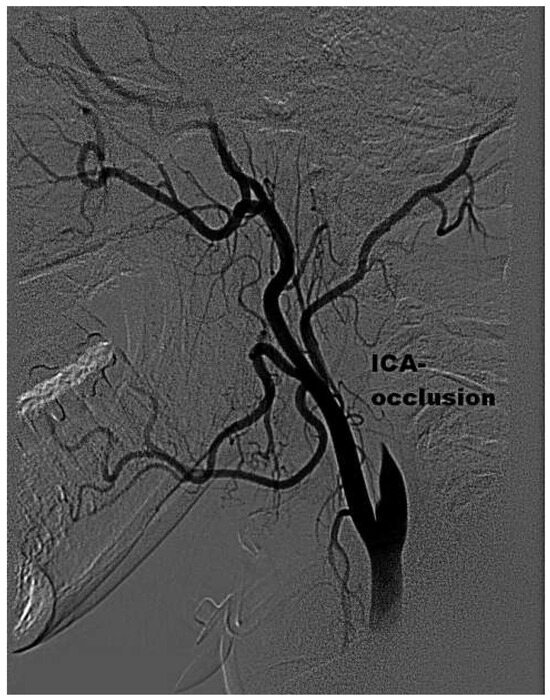

Mechanical Thrombectomy After Embolic Internal Carotid Artery Occlusion in Acute Stroke

by Christophe A. Wyss, Anahita Dastoor and Roberto Corti

Cardiovasc. Med. 2014, 17(2), 51; https://doi.org/10.4414/cvm.2014.00204 - 19 Feb 2014

A 34-year old woman presented to the emergency department with a wake-up stroke, after onset of a sensomotoric paresis of the right arm and motoric aphasia [...] Full article

Figure 1